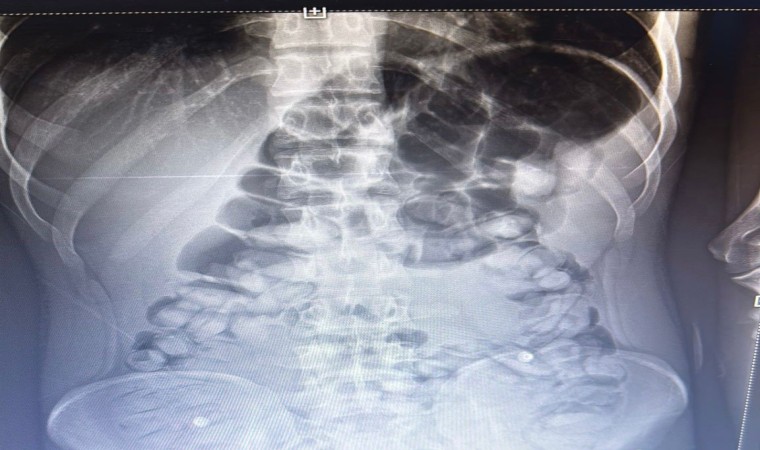

Erzurum Emniyet Müdürlüğü Narkotik Suçlarla Mücadele Şube Müdürlüğü ekipleri tarafından yapılan operasyonda bir şahsın karnından 1 kg 134 gram Afyon Sakızı maddesi çıkarıldı.

Emniyet Müdürlüğü tarafından konu ile ilgili yapılan açıklamada şöyle denildi,” Uyuşturucu madde ticareti ve sevkiyatına yönelik yapılan çalışmalar neticesinde 13.11.2023 tarihinde tespit edilen yolcu otobüsünde durumunlarından şüphelenilenerek uyuşturucu madde yutmuş olabileceği değerlendirilen ve İlimiz Şehir Hastanesinde iç beden muayenesi yaptırılan S.A. (2006 doğumlu) isimli şahıstan toplam 1 kg 134 gram Afyon Sakızı maddesi ele geçirilmiş, konuyla ilgili adli mercilere sevk edilen şahıs tutuklanarak cezaevine teslim edilmiştir. Uyuşturucu veya uyarıcı madde satışı, kullanımı ve nakli ile ilgili mücadelemiz kararlılıkla sürdürülecektir.”